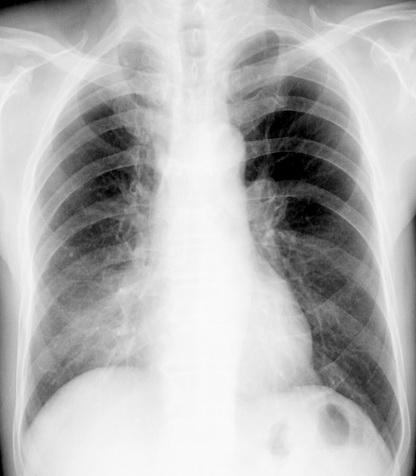

考虑右肺中叶不张,请大家发表意见

右肺中叶不张、肺门轮廓增大,占位不除外;建议增强,必要时支气管镜详查。

右肺中叶支气管闭塞,中叶肺不张,右侧肺门见肿块影。中心型肺癌的可能大。建议支气管镜检查。

右中叶体积明显缩小,且其支气管未显示,先考虑:中心型肺癌班右中叶肺不张。

建议:支气管镜检查。

考虑右肺中叶中央型肺癌并右肺中叶肺不张;建议:行纤支镜检查。

右肺门旁类圆形肿块影,右肺中叶不张,建议纤支镜检查。

1右肺门旁类圆形肿块影,右肺中叶不张,建议纤支镜检查

平片就可以诊断右肺中叶不张,做CT就是要找原因!中叶支气管开口不清,建议支气管镜检查。